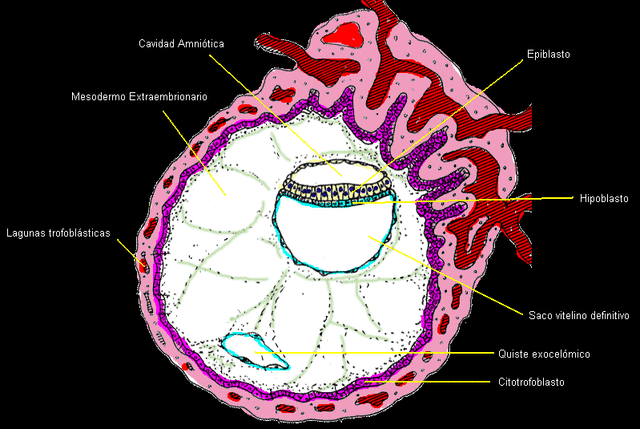

En el comienzo de la segunda semana de desarrollo embrionario, tras el contacto del blastocisto con el endometrio se produce la proliferación del trofoblasto del polo embrionario dando lugar a una masa de células sin membrana conocidas con el nombre de sincitiotrofoblasto. Por el contrario, las células del trofoblasto que forman la pared del blastocisto conservan sus membranas constituyendo el citotrofoblasto. .